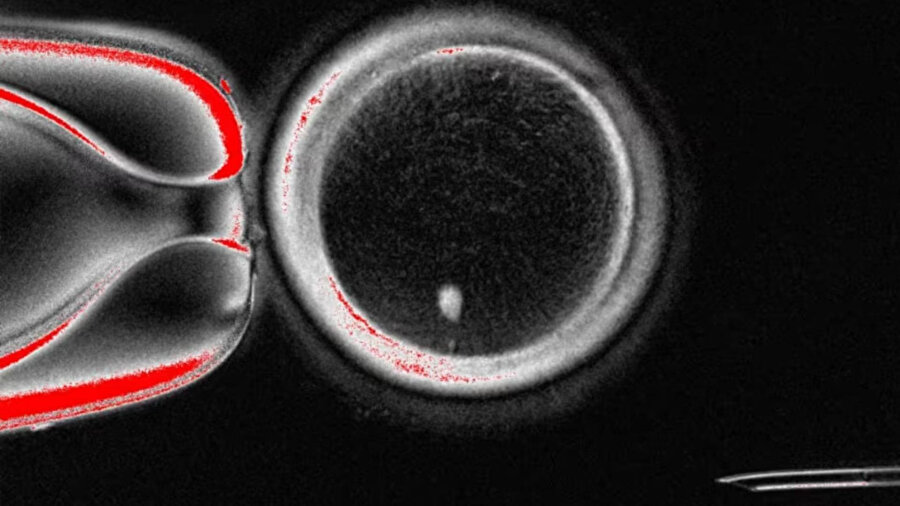

Salı günü yayınlanan çalışma, bu işlemin,insan derisinden genetik bilgilerin çoğunu içeren hücre çekirdeğini alıp kendi çekirdeğinden arınmış donör yumurtasına transfer ederek gerçekleştiğini bildirdi. Araştırmacılar toplam 82 tane kullanışlı yumurta hücreleri yetiştirebildi.

Deri hücresini sunan kişiyle DNA paylaşan ve başka bir bireyin spermiyle döllenebilen bir yumurta elde edilen bu sonuç, kısırlık tedavisi için oldukça büyük bir gelişme fakat tekniğin kilinik olarak kullanılabilmesi için en az 10 yıl geçmesi gerekiyor.